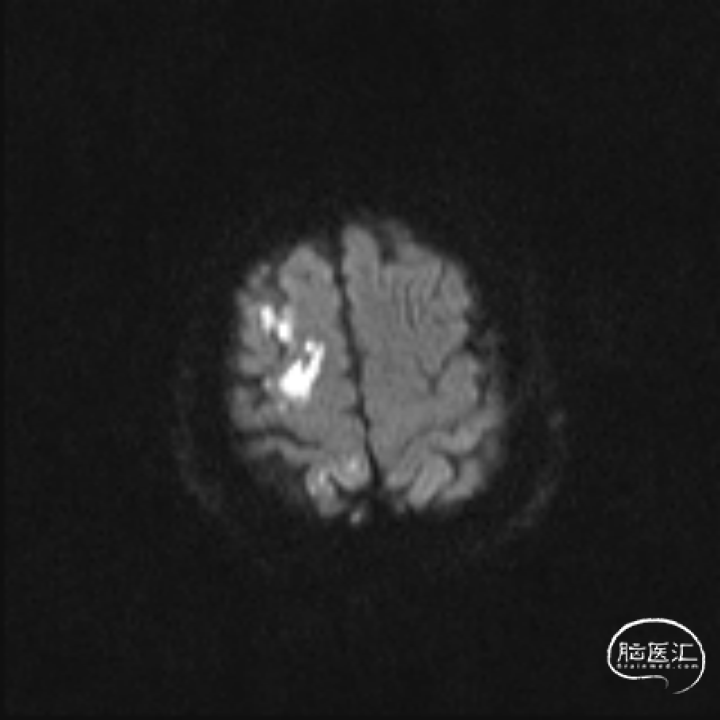

入院时头部 DWI+MRA(7h)

右侧顶叶新发脑梗死。右侧颈内动脉及大脑中动脉闭塞。